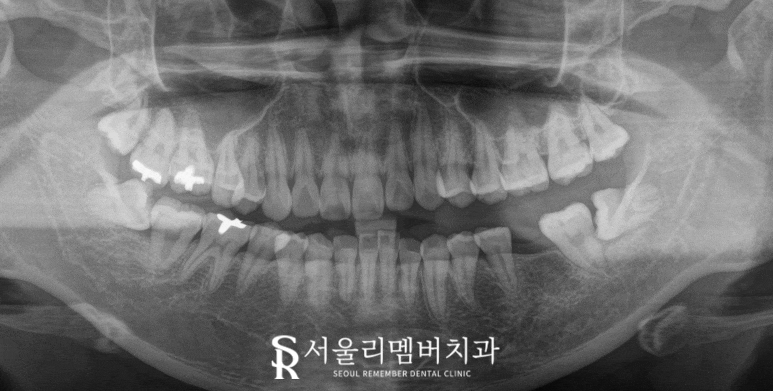

오늘 사당 치과 에서 설명드리는 케이스에서는

왼쪽 아래 두 번째 작은 어금니(35번)이 상실되어 있고

좌우위아래 4개의 사랑니는 모두 존재하고 있었습니다.

치아 결손은

저작 기능 저하,

인접치의 이동, 대합치의 정출 같은

많은 문제를 야기할 수 있습니다.

특히 제2소구치는 저작 기능에 중요한 역할을 하므로,

결손 시 적절한 보철 치료가 필요합니다.

2024.08.11

사당 치과 에서 보여드리는 사진에서도

비어있는 작은 어금니와

맨 뒤 제3대구치의 존재가 확인되며

이대로 두면 글의 서론에서 설명드린 것과 같은

여러 문제가 나타날 수 있기에

임플란트를 먼저 심고

회복 기간 동안에는 순서대로

제3대구치를 발치하여

예방적인 진료를 해주는 것이 좋겠습니다.